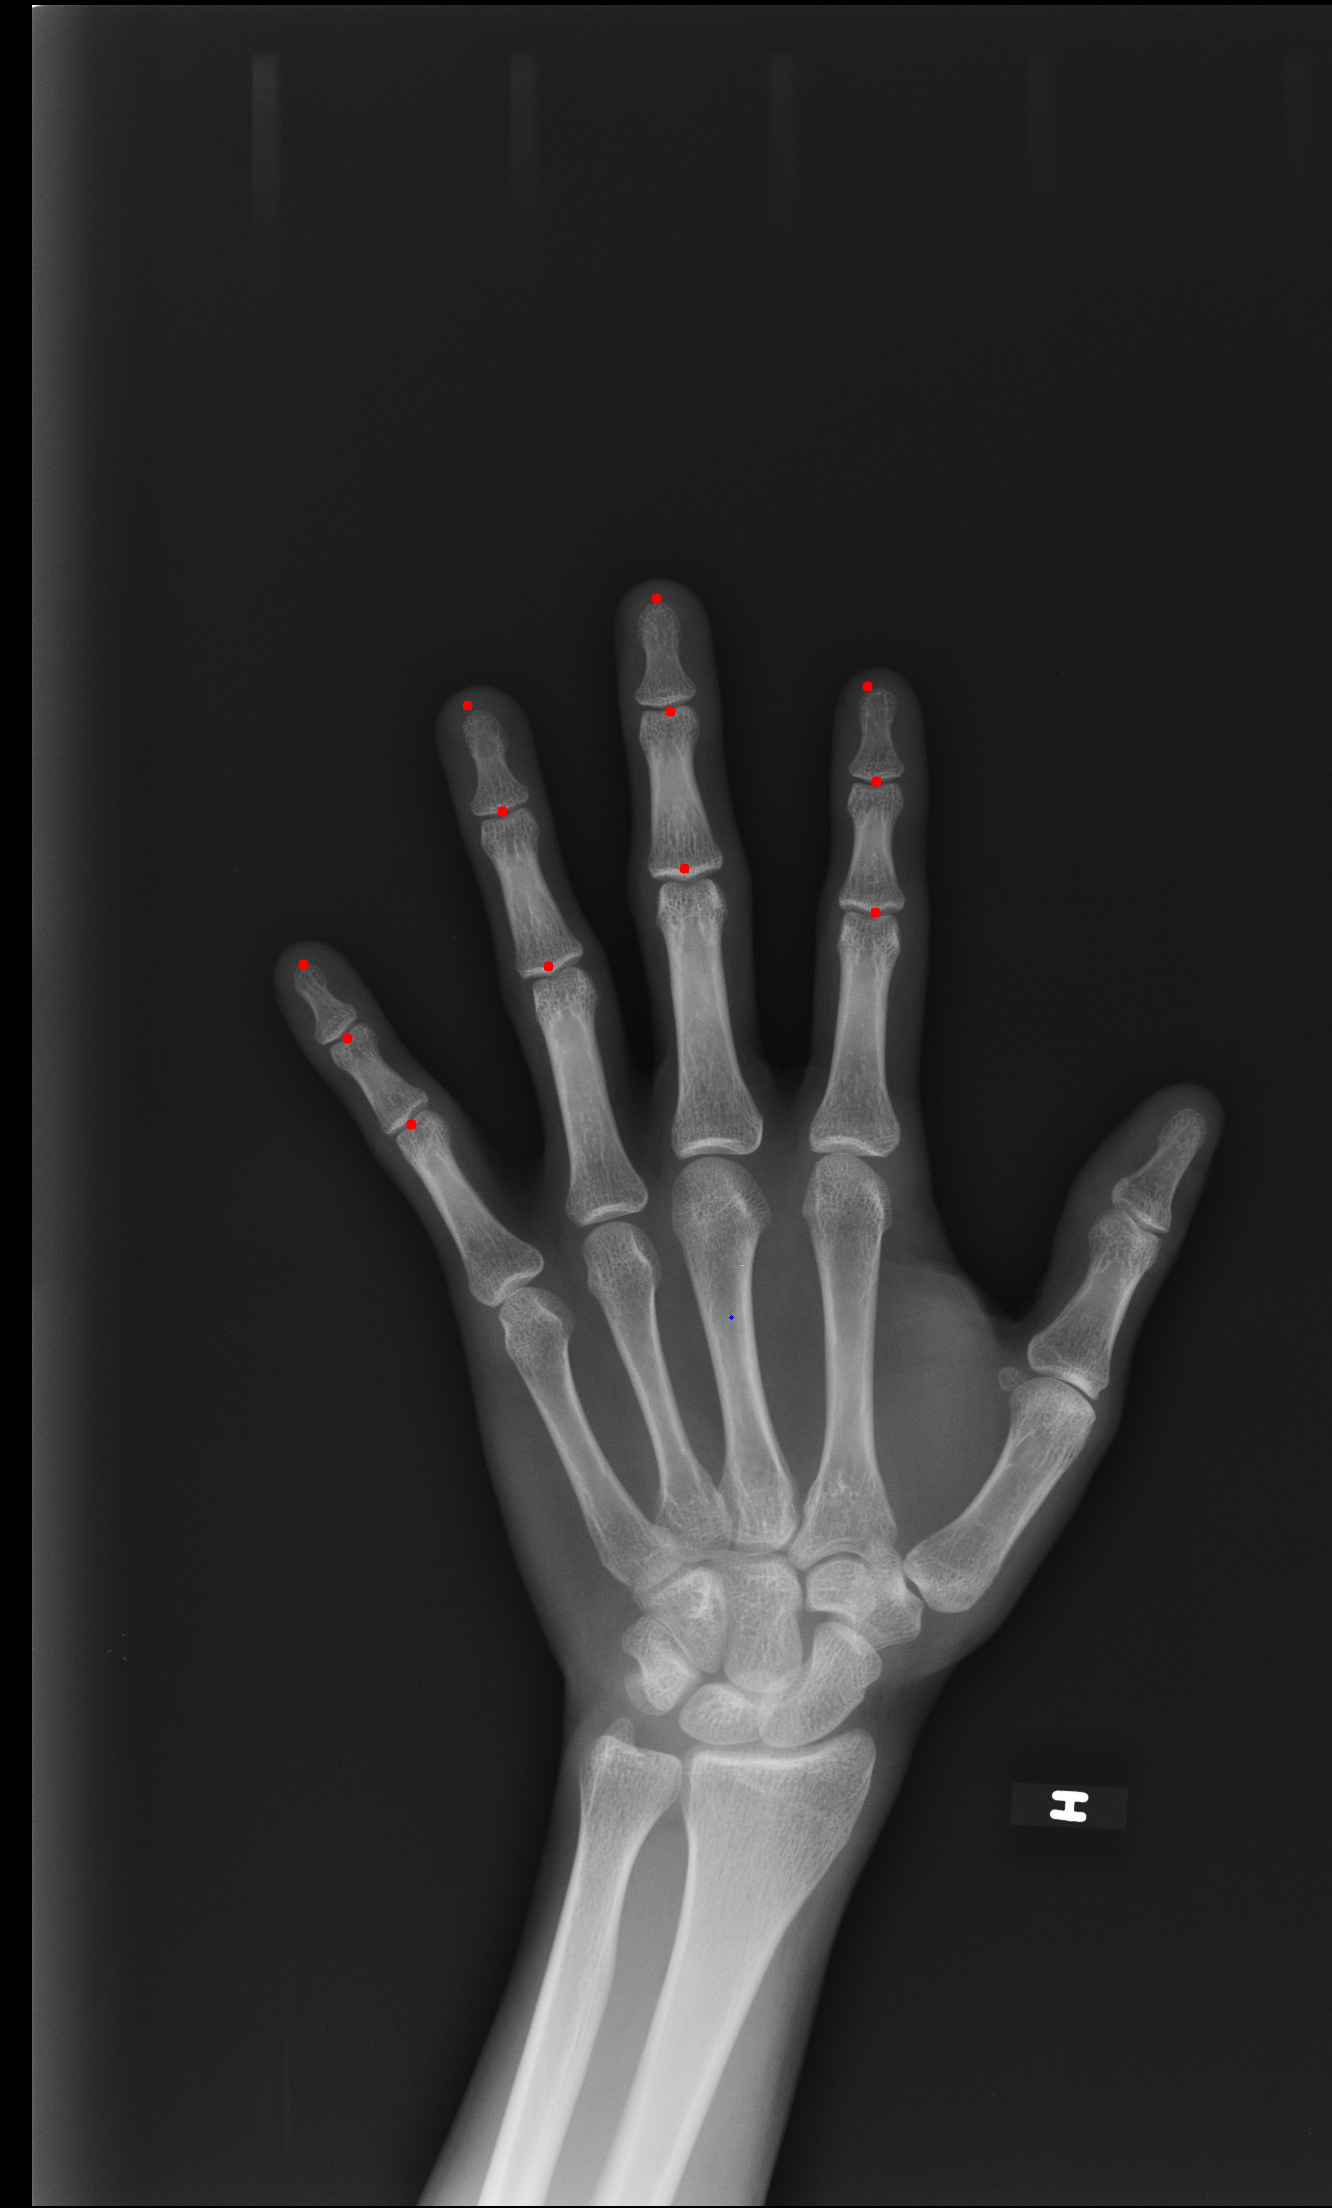

Labeling of finger landmarks in hand xrays.

Finger landmark labeling for left handed x-ray images

This project uses two algorithms (symbolic and neural) to extract finger landmarks from left hand x-rays. It's intended to be used as an auxiliary tool for forensics research at UNAM.

Note that the symbolic algorithm only approximates landmarks in four fingers (not including the metacarpophalangeal joints).